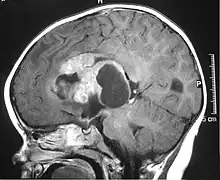

![]() | |

| MRI of an AT/RT | |

The initial diagnosis of a tumor is made with a radiographic study (MRI[22] or CT-). If CT was performed first, an MRI is usually performed as the images are often more detailed and may reveal previously undetected metastatic tumors in other locations of the brain. In addition, an MRI of the spine is usually performed. The AT/RT tumor often spreads to the spine. AT/RT is difficult to diagnose only from radiographic study; usually, a pathologist must perform a cytological or genetic analysis.

Appearance on radiologic exam

AT/RTs can occur at any sites within the CNS; however, about 60% are located in the posterior fossa or cerebellar area. The ASCO study showed 52% posterior fossa; 39% sPNET; 5% pineal; 2% spinal, and 2% multifocal.[3]

The tumors' appearance on CT and MRI are not specific, tending towards large size, calcifications, necrosis (tissue death), and hemorrhage (bleeding). Radiological studies alone cannot identify AT/RT; a pathologist almost always has to evaluate a brain tissue sample.

The increased cellularity of the tumor may make the appearance on an uncontrasted CT to have increased attenuation. Solid parts of the tumor often enhance with contrast MRI finding on T1 and T2 weighted images are variable. Precontrast T2 weighted images may show an isosignal or slightly hypersignal. Solid components of the tumor may enhance with contrast, but not always. MRI studies appear to be more able to pick up metastatic foci in other intracranial locations, as well as intraspinal locations.